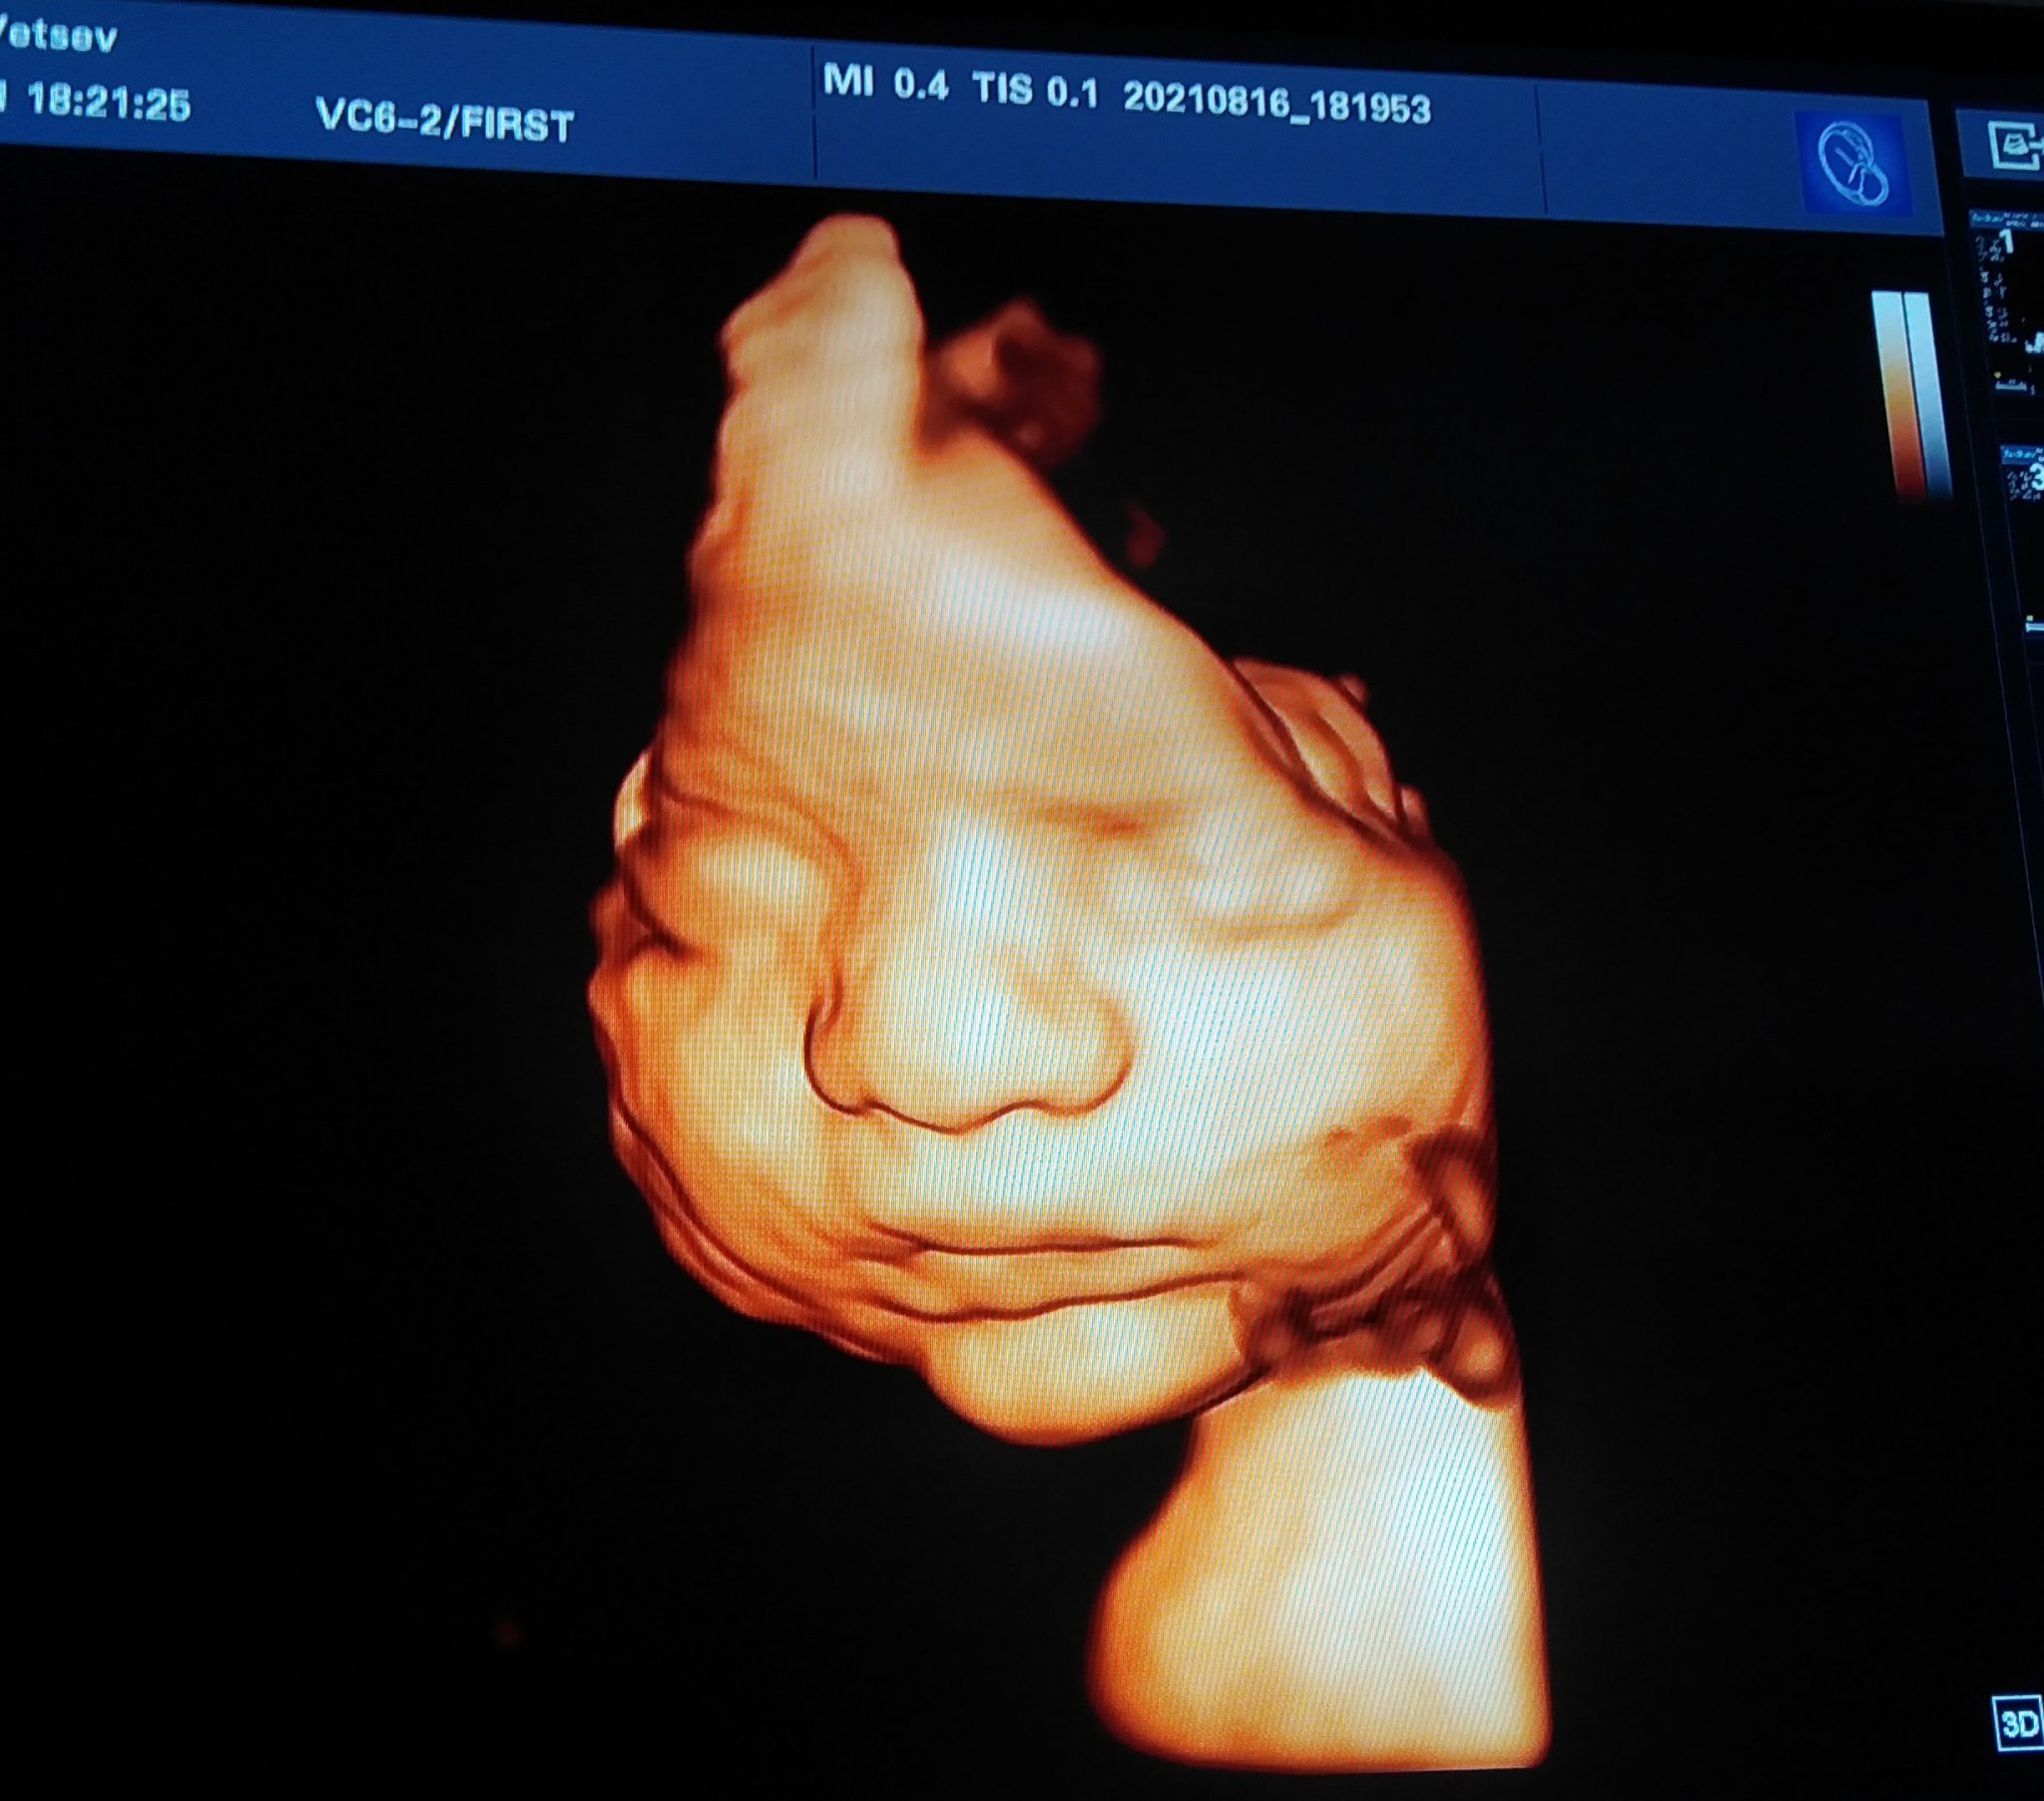

Аз немога да си намеря място от щастие!

Прегледа мина добре и бебето беше с лице и познайте..... Застана като менекен

1,600 без няколко грама

Водите са много и да спра сладкото, което е по 1 вафла на седмица например

30 седмица съм

Искам да покажа и една друга снимка

На баткото